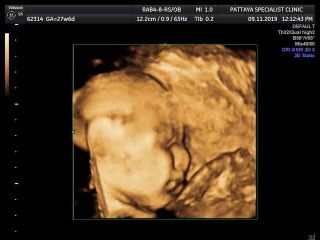

ขอดูเพื่อนๆหนูหน่อยค่ะ?️ เราเป็นผู้หญิงนะ?คุณแม่ท่านไหนได้ลูกสาวบ้างค่ะ☺️???